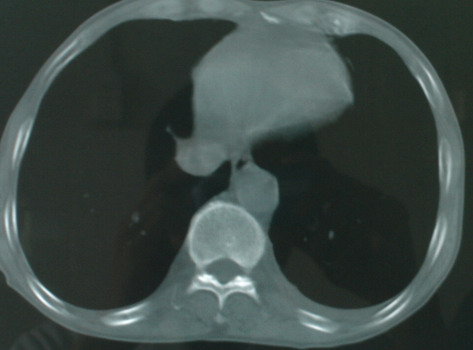

以下是引用医影拾贝在2008-6-3 18:48:00的发言:[br]双上肺弥漫性小结节影,纵隔窗内钙化淋巴结影,考虑血播性tb可能性较大,不除外肺ca可能

以下是引用卜一在2008-6-3 19:33:00的发言:[br]双肺结节,以双上肺分布为多,期间搀杂片状致密影及索条致密影。考虑:继发性肺结核伴血型播散可能性大。不除外肺泡ca的可能!另:椎体退变!

以下是引用panyishengct在2008-6-3 21:09:00的发言:[br]双上肺弥漫性小结节影,纵隔窗内钙化淋巴结影,考虑矽肺或/和tb可能性较大,不除外肺ca可能。腰椎考虑退变。 [br][br]